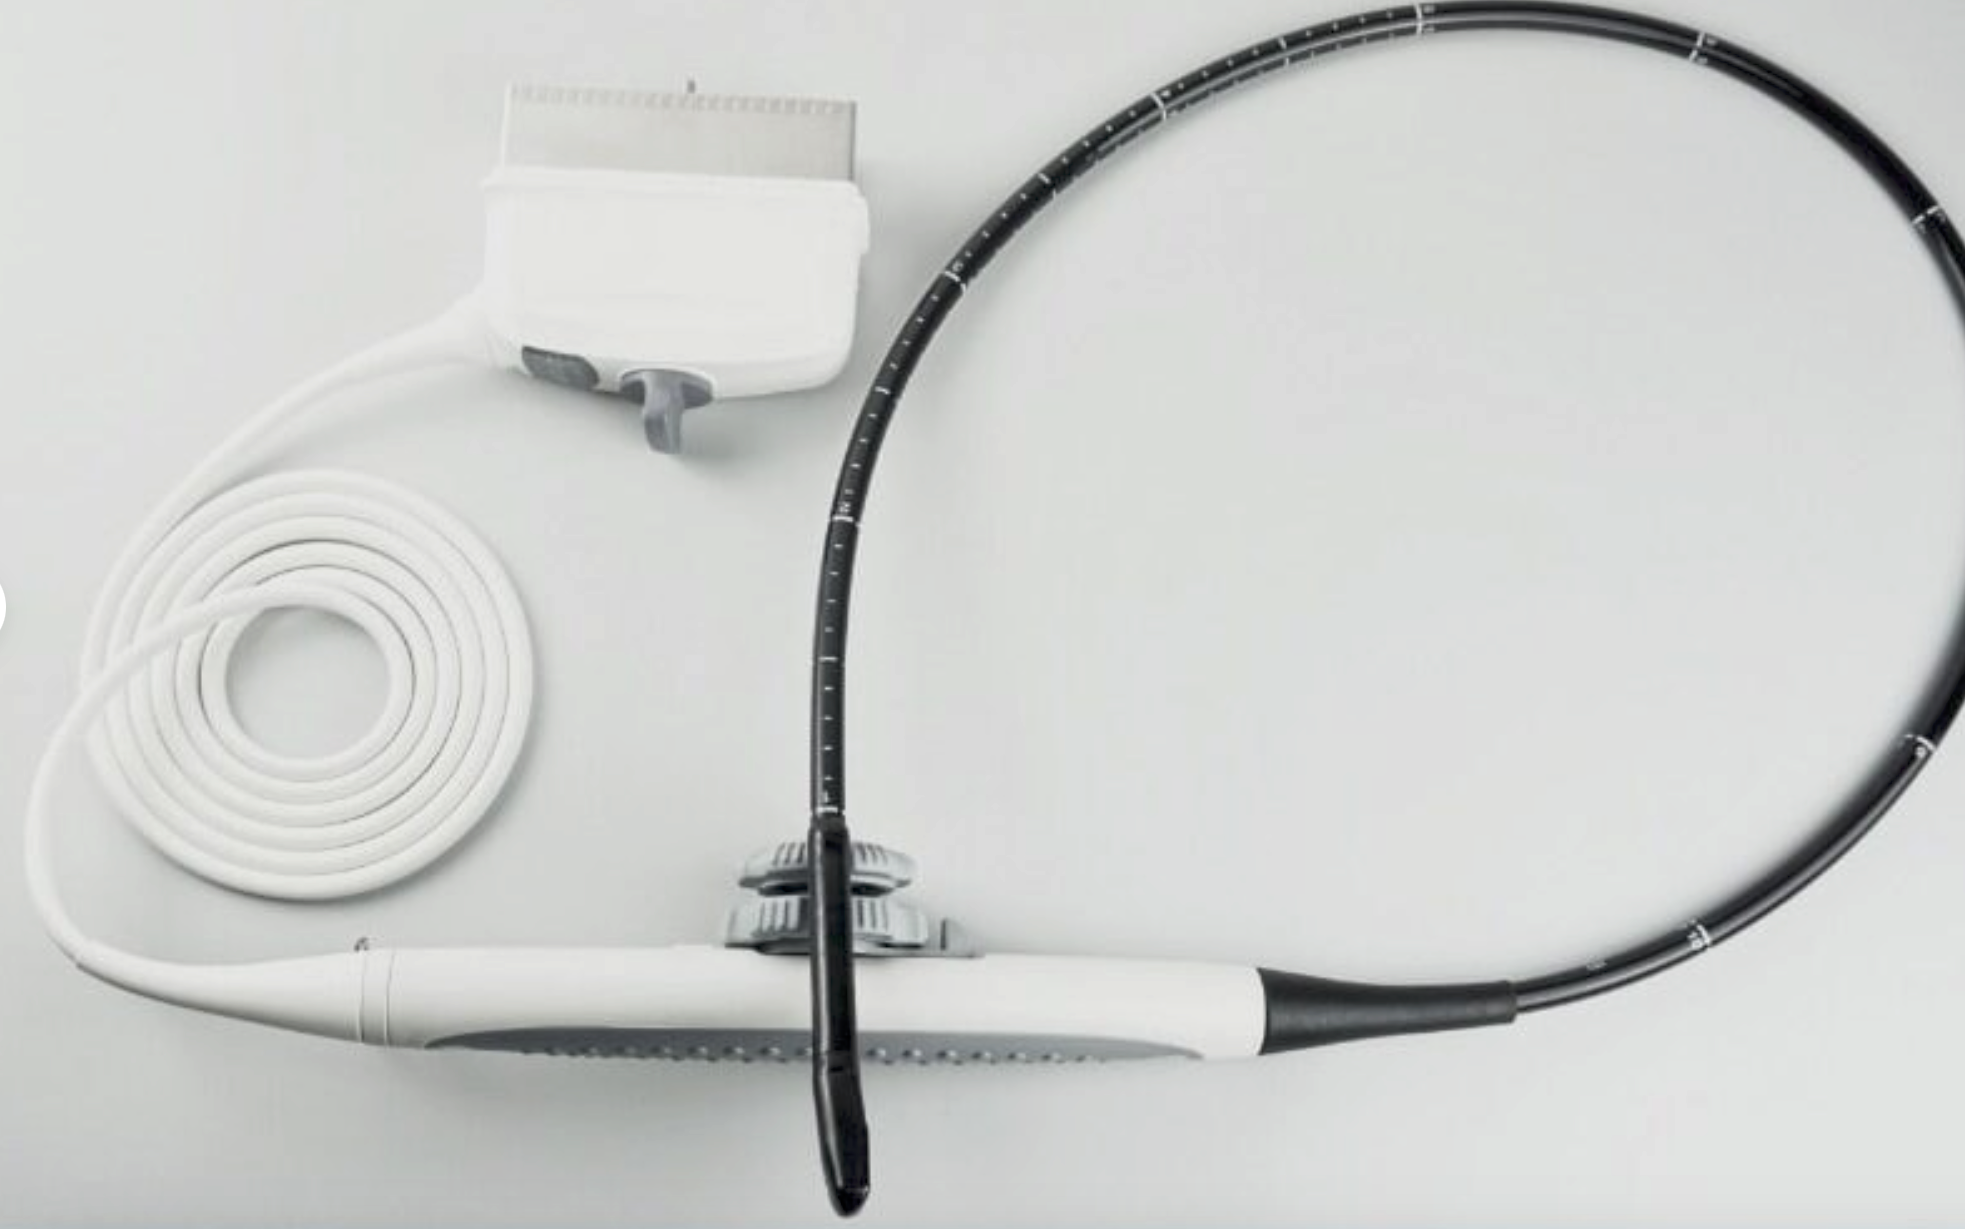

Description

Condition:Manufacturer refurbished : An item that has been professionally restored to working order by a manufacturer or manufacturer-approved vendor. This means the product has been inspected, cleaned, and repaired to meet manufacturer specifications and is in excellent condition. This item may or may not be in the original packaging. See the sellerâs listing for full details. See all condition definitions- opens in a new window or tab

Seller Notes:âGreat Condition!! - Manufacturer (GE) Refurbished!!â

Brand: LOGIQ E